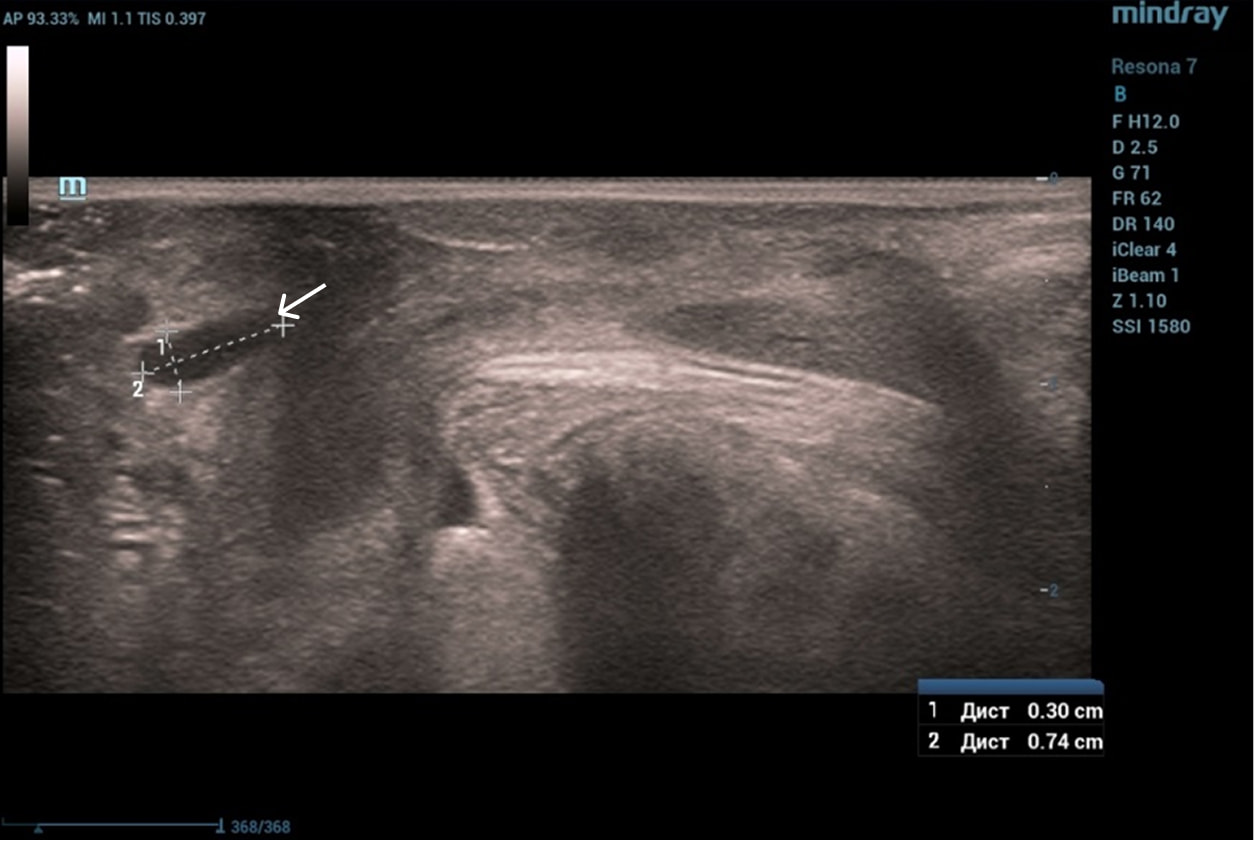

Осмотр: периуретрально визуализируется мягко-эластичное образование размерами 0,5×0,5 см.

Диагноз: хронический цистит (посткоитальный). Дистопия уретры. Опущение передней стенки влагалища I степени. Состояние после периуретрального введения геля на основе гиалуроновой кислоты.